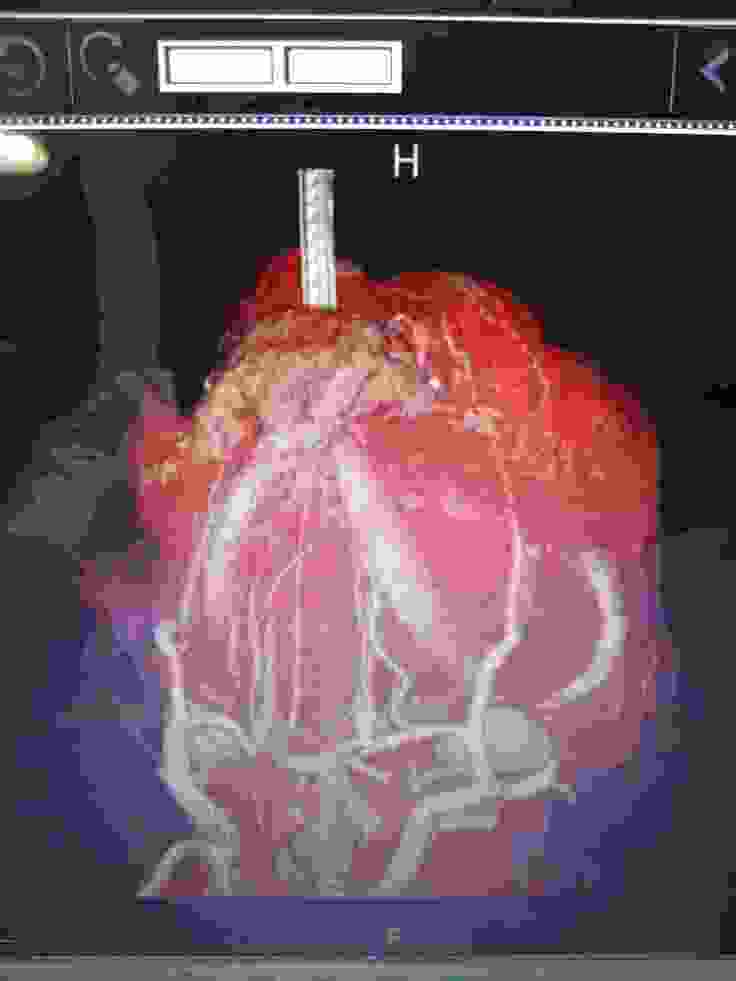

CT検査画像

パグのジョー(15歳)が悪性黒色腫(ステージ4)を発症し、進行のとても早いガンで既に肺に転移している状態で、手術はもう出来ない状態だと言われました。数年前から後両足が弱り現在は自力での歩行はできません、膀胱炎や急性肝炎など入退院を繰り返しようやく最近では体調が少し安定してきたかなと思った矢先に、御飯が左側の口からよくこぼれるようになってなにげに顎の下を触ると少し腫れているのに気づき、すぐに病院で診察してもらいましたが、詳しい検査をしないと分からないとのことで、腫瘍専門がある病院を紹介してもらい、造影剤を使用したCT検査、組織検査の結果、口腔悪性黒色と診断され腫瘍の大きさや肺に迄転移していることから手術は出来ないとのことで放射線治療しか有効な治療はないと言われました。ガンの進行が早く、何も治療をしないと口腔が壊死していく可能性があると説明され、根治は困難ですが、せめて最後迄御飯を食べてもらいたいと思い、放射線治療をしてあげたいと思いました。しかし、高額の検査費と治療費の為、放射線治療するのはかなり困難と半ば諦めていた時に、この活動を知り、せめてもう少しでもジョーとの時間を過ごせるように、皆様のご支援よろしくお願いいたします。

CT検査(造影剤)